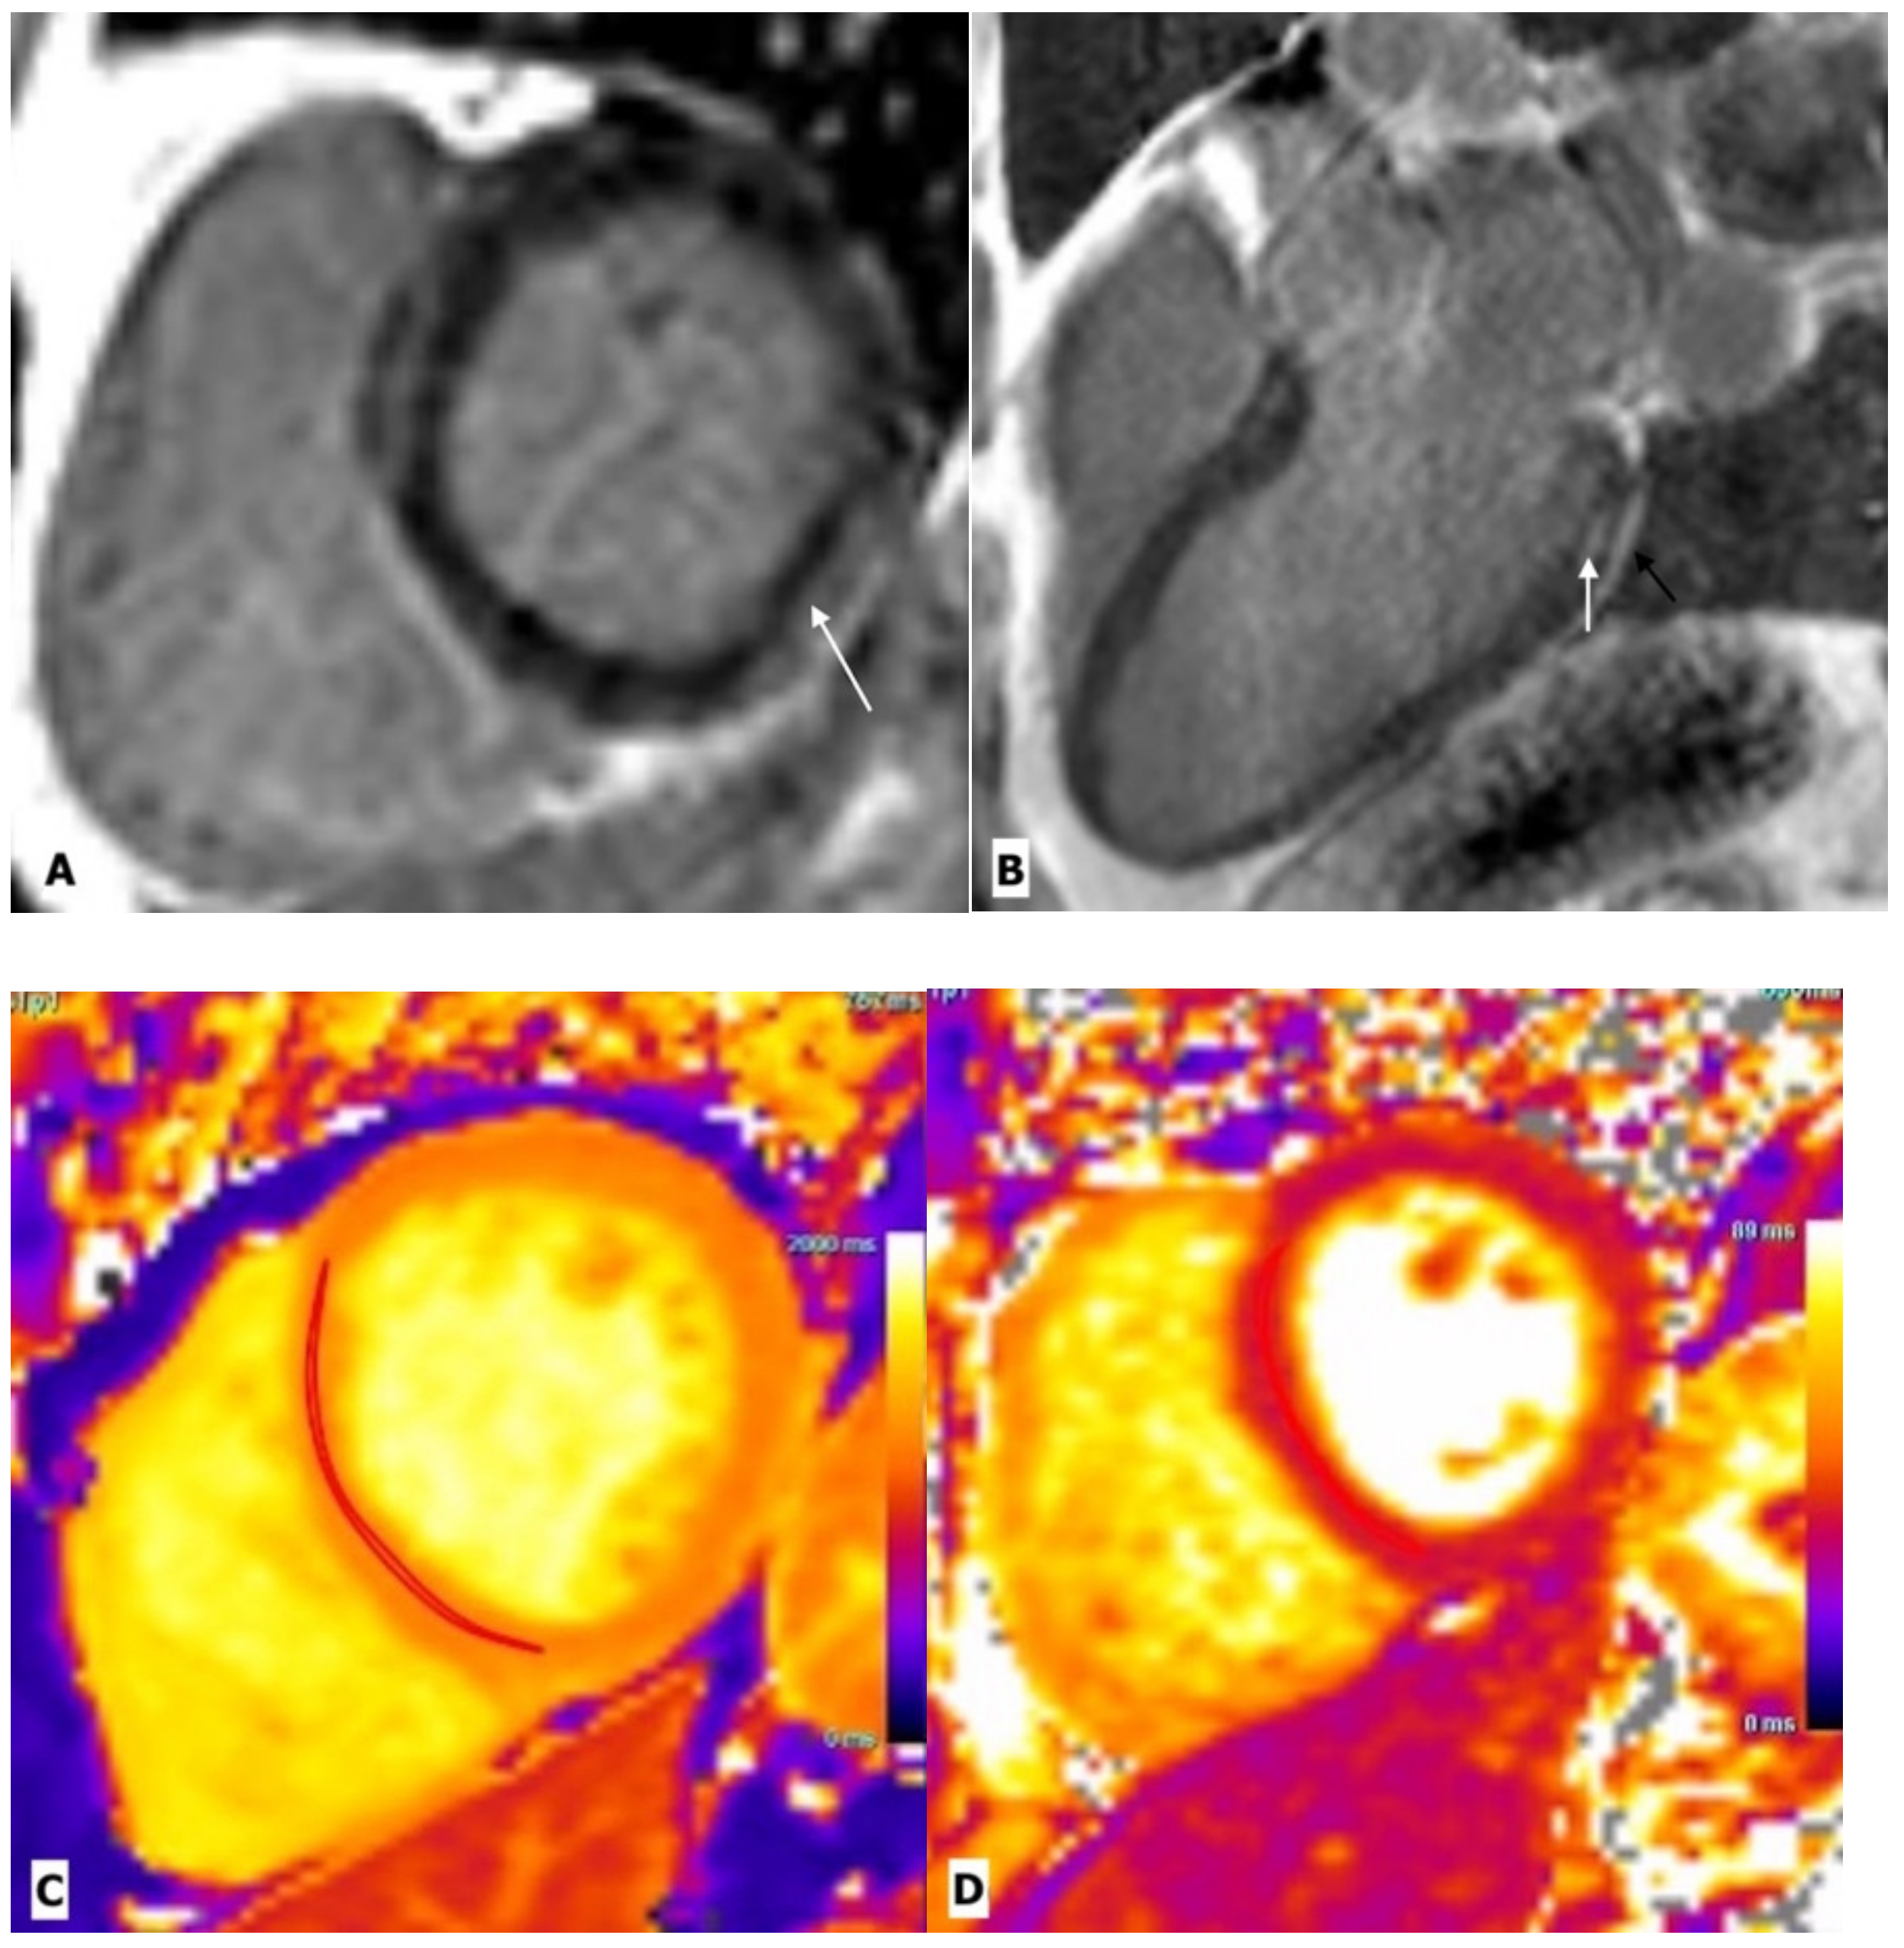

| Myocarditis | Luetkens, J.A. et al. | Prospective cohort study | 28 patients and 22 control subjects | CMR | Compared with healthy controls, HIV-infected patients showed lower ejection fraction, lower global strain values, elevated native T1 and T2 values, and myocardial fibrosis, predominantly at the subepicardial of the midventricular and basal inferolateral wall. |

| Ntusi, N. et al. | Cross sectional observational study | 103 patients and 92 control subjects | CMR | Compared with controls, HIV-infected patients had lower LVEF, higher myocardial mass, lower peak diastolic strain rate, and higher native T1 values. Pericardial effusions and myocardial fibrosis were 3 and 4 times more common, respectively, in subjects with HIV infection. | |

| Robbertse et al. | Prospective study | 73 patients and 22 healthy controls | CMR | Compared with controls, a significant decrease in native T1 and ECV was seen after 9 months of HAART in HIV patients, which was significantly associated with a decrease in C-reactive protein, a decrease in HIV viral load, and an improvement in CH4 count. | |

| De Leuw et al. | Prospective observational study | 156 patients | CMR | Patients with higher ECV values have a higher rate of cardiovascular outcomes. | |